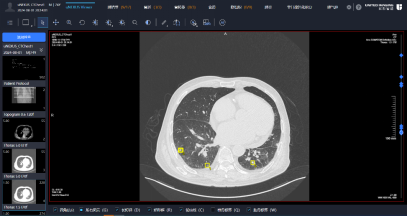

联影智融 uInterv C550 经皮介入手术机器人可广泛应用于放射介入科、胸 外科、呼吸科、肝胆外科、肿瘤中心等临床科室,为肺、肝脏、肾脏、胰腺等胸 腹部器官的经皮穿刺等肿瘤相关治疗提供精准的器械控制操作,实现 CT 实时可 视化成像模式下的“实时可见,边看边穿“,解决了临床中的“盲穿”痛点,以 及定位、导航类手术辅助设备的临床局限。